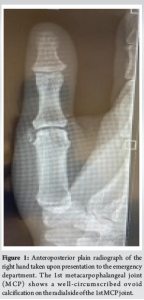

A 39-year-old female general practitioner presented to the emergency department (ED) after developing severe thumb metacarpophalangeal pain and swelling in her right dominant hand. A slight pain over the radial aspect of the first metacarpal was noticed 5 months before her acute hospital attendance. The patient initially suspected it to be a repetitive strain injury and managed by avoiding thumb use and movement. Five days before presenting, the patient reported severe pain and swelling over the base of the first metacarpal when using her keyboard and performing mother–baby checks at work. There was no history of trauma and symptoms worsened significantly over the 5 days. On examination, she was apyrexial. She had swelling and tenderness at the base of the thumb. Mild erythema was detected around the thenar eminence and in the webspace between the first and second metacarpals on the palmar side of the right hand. All ranges of motion of her thumb were reduced and reproduced severe pain. She was neurovascularly intact distally. All other metacarpals had a full range of motion without pain. Blood tests undertaken acutely were normal (full blood count [FBC] and C-reactive protein [CRP]), with a low concern of infection. The subsequent X-ray was ordered upon her presentation to the ED and was used to discern the cause of her presenting pain. Our patient’s X-ray (Fig. 1) shows calcific periarthritis and juxta-articular deposits of formless calcium hydroxyapatite, on the radial side of the thumb 1st MCP joint in the right hand (thumb). The patient has hypermobility of the thumb, which has led to poor positioning of the joint during functional tasks, such as typing and writing. This is evident from the presence of a writer’s callus on the 2nd finger of this patient’s right hand.

Painter first described painful periarticular soft-tissue calcium deposits in 1907 [2]. Further research has led to a variety of nomenclature, including calcareous tendinitis, pseudopodagra, and rheumatism [1,3,4]. Cases tend to be monoarticular and self-limiting with tendons in the shoulder being most frequently affected. ACP of the hand and wrist have been described in adult [3-5] and pediatric [6] populations, with the most common mechanism of injury involving flexor carpi ulnaris when in close proximity to the pisiform bone. Our case highlights a connection between chronic behavioral patterns and the development of ACP, emphasizing the need to consider ACP as a possible diagnosis in patients with these behavioral patterns [7]. ACP of the thumb is commonly misdiagnosed due to its comparably low prevalence in the hand and clinical features that mimic more common conditions, such as various infections. Diagnosis of ACP in this case required radiographic evidence to rule out other conditions that should be considered from this clinical presentation such as cellulitis plus reactive arthritis, septic arthritis, deep thenar space infection, gout, heterotopic ossification (HO), and pseudogout (calcium pyrophosphate deposition disease (CPPD) [2,8,9]. When diagnosing ACP, both clinical and radiological findings must be considered together. Based on the clinical findings alone infection would be the most probable diagnosis [8]. However, normal blood tests (FBC and CRP) and the presence of periarticular calcification on the radiograph, would make this less likely [10]. Radiographs may show calcification in both gout and ACP. However, gout most commonly affects the first metatarsophalangeal joint. Furthermore, periarticular erosions may occur in calcific periarthritis [4], resulting in ACP as the most likely diagnosis. The cortex and internal trabeculations that are typically seen in HO are not present in cases of ACP, and the calcification caused by ACP is not consistent with that of the typical chondrocalcinosis seen in CPPD [4]. Calcific periarthritis is usually managed conservatively using non-steroidal anti-inflammatory drugs, rest, immobilization of the joint, physiotherapy, and local steroid injections [1]. If conservative management fails, needle aspiration/“dry needling,” shock-wave therapy and in some rare cases surgical treatment can be considered [1,2]. Conservative management is the first-line treatment and patients commonly find reduced symptoms 4–7 days after the acute presentation of pain [1,3]. Interventions must strive to sustain or advance the patient’s quality of life with the condition.